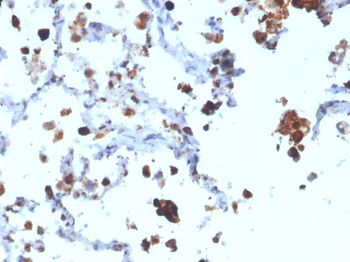

Immunohistochemistry of paraffin-embedded Human colon cancer tissue using NAPA antibody

Immunohistochemistry of paraffin-embedded Human liver cancer tissue using NAPA antibody